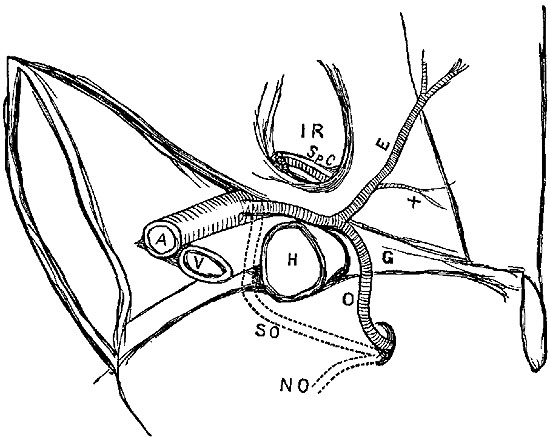

| 1. | Ligature of Aorta—Sir A. Cooper's incision. |

| 2. | Ligature of Aorta—South and Murray's incision. |

| 3. | Ligature of Common Iliac. |

| 4. | Ligature of External Iliac—Sir A. Cooper's. |

| 5. | Ligature of Femoral in Scarpa's triangle. |

| 6. | Ligature of Femoral below Sartorius.[1] |

| 7. | Ligature of Innominate. |

| 8. | Ligature of third part of Left Subclavian. |

| 9. | Ligature of Axillary in its first part. |

| 10. | Ligature of Axillary in its third part. |

| 11. | Ligature of Brachial. |

1. A straight incision (Plate I. fig. 1) in the linea alba, just avoiding the umbilicus by a curve, and dividing the peritoneum, allows the intestines to be pushed aside, and the aorta exposed still covered by the peritoneum, as it lies in front of the lumbar vertebræ. The peritoneum must again be divided very cautiously at the point selected, and the aortic plexus of nerves carefully dissected off, in order that they may not be interfered with by the ligature. The ligature should then be passed round, tied, cut short, and the wound accurately sewed up.

A curved incision (Plate I. fig. 2), with its convexity{3} backwards, from the projecting end of the tenth rib to a point a little in front of the anterior superior spinous process of the ilium. At first through the skin and fascia only, this incision must be continued through the muscles of the abdominal wall, one by one, till the transversalis fascia is exposed, which must then be scraped through very cautiously, so as not to injure the peritoneum, which is to be detached from the fascia covering the psoas and iliacus muscles, and must be held inwards and out of the way by bent copper spatulæ. The common iliac will then be felt pulsating, and on it the finger may easily be guided up until the aorta is reached.

Incision.—(Plate I. fig. 3.)—From a point about half an inch above the centre of Poupart's ligament, a crescentic incision should be made, at first extending upwards and outwards, so as to pass about one inch inside of the anterior superior spine of the ilium, and then prolonged upwards and inwards, as far as may be rendered necessary by the size of the aneurism or the depth of parts. It must extend through skin and superficial fascia, exposing the tendon of the external oblique, which must then be slit up to the full extent visible. The spermatic cord may then be easily exposed under the edge of the internal oblique, and the forefinger of the left hand inserted on the cord, and thus beneath the internal oblique and transversalis muscles, the peritoneum being quite safe below.

The higher operation (Abernethy's modified).—An incision must be made through the skin about four inches in length, but longer in proportion to the amount of{9} subcutaneous fat, and the depth of the pelvis, extending from a point one inch to the inside of the anterior superior spine of the ilium, to a point half an inch above the middle line of Poupart's ligament. It must be slightly curved, with its convexity looking outwards and downwards.[3]

The operation from below (Plate I. fig. 4), Sir Astley Cooper's, is thus described by Mr. Hodgson:[4]—"A semilunar incision is made through the integuments in the direction of the fibres of the aponeurosis of the external oblique muscle. One extremity of the incision will be situated near the spine of the ilium; the other will terminate a little above the inner margin of the abdominal ring. The aponeurosis of the external oblique muscles will be exposed, and is to be divided throughout the extent, and in the direction of the external wound. The flap which is thus formed being raised, the spermatic cord will be seen passing under the margin of the internal oblique and transverse muscles. The opening in the fascia which lines the transverse muscle through which the spermatic cord passes, is situated in the mid space between the anterior superior spine of the ilium and the symphysis pubis. The epigastric artery runs precisely along the inner margin of this opening, beneath which{11} the external iliac artery is situated. If the finger therefore be passed under the spermatic cord through this opening in the fascia, it will come in immediate contact with the artery which lies on the outside of the external iliac vein. The artery and vein are connected by dense cellular tissue, which must be separated to allow of the ligature being passed round the former."

Operation of Ligature of the Femoral—Scarpa's Space.—The patient being placed on his back, and being brought very thoroughly under chloroform, the knee of the affected limb should be bent at an angle of about 120°, and supported on a pillow. Having previously ascertained the angle of junction of the sartorius and adductor, the surgeon should make an incision (Plate I. fig. 5) just over the pulsations of the vessel, in the middle line of the space, having its lower end quite over the sartorius muscle, and its upper one, at a distance from two and a half to three and a half inches, varying according to the amount of fat and muscle. The saphena vein can generally be recognised, and is almost always safe out of the way of this incision at its inner side.

The limb being laid as before on the outside, and slightly bent, the skin shaved and the pulsation of the artery detected, an incision (Plate I. fig. 6) must be made from the lower edge of the sartorius muscle just as it crosses the vessel, along the course of the vessel, avoiding if possible the internal saphena vein.

Operation.—The patient lying on his face, a straight{23} incision (Plate III. fig. 1), at least four inches in length, should be made over the artery, and thus nearer the inner than the outer hamstring; a strong fibrous aponeurosis will require division after the skin and superficial fascia are cut through, the limb is then to be flexed, and the tendons drawn aside with strong retractors; fat and lymphatic glands must next be dissected through, and then the vein and artery, lying on a sort of sheath of condensed cellular tissue, are seen, the vein lying above the artery and obscuring it. The vein must be drawn to the outside, and the thread passed round the artery, which lies close to the bone, on the ligamentum posticum of Winslowe.

The patient lying down with the shoulders raised and head thrown well back, the sternal attachment of the right sterno-mastoid must be very freely exposed. This may be done by an incision (Plate I. fig. 7) along its anterior edge from the upper edge of the sternum, as far as may be necessary; another about the same length along the upper edge of the clavicle, will meet the former at an acute angle, and will include a triangular flap of skin, which must be carefully dissected up. The sternal, and probably a portion of the clavicular attachment of the right sterno-mastoid, must then be cautiously divided. This being done, the sterno-hyoid and sterno-thyroid muscles require division immediately above their sternal attachments.

Ligature above Omohyoid.—Using the anterior border of the sterno-mastoid as a guide, but leaving it gradually above to a little nearer the mesial line, an incision (Plate IV. fig. 1), varying in length according to the depth of fat and cellular tissue in the neck, but with its central point opposite the upper border of the cricoid cartilage, must be made through skin, platysma, and superficial fascia. While making the incision the head should be held back, and the face slightly turned to the opposite side; the parts being now relaxed by position, the edges of the wound must be held apart by blunt hooks or copper spatulæ, and the deep fascia carefully divided over the vessel, which will be recognised by the pulsation. It may be noted here that even in thin subjects the sterno-mastoid edge invariably overlaps the vessel, though in many anatomical diagrams it would appear to be in part subcutaneous.